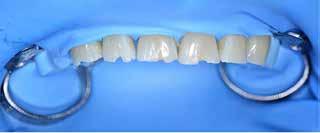

Behandling af lokaliseret anteriort tandslid med fast bidskinne ad modum Bjørn Dahl

Fig. 2. A. Indprøvning af tilpassede Odus Pellakroner anvendt som matricer. B. For at opnå god æstetik blev Odus Pellakronerne fyldt med plast med lagteknik: a) 1. lag af transparent plast (emalje A1) blev lagt facialt i matricen i en tykkelse på ca. 1 mm. b) 2. lag af opak, men lys plast (dentin A1) blev lagt i den incisale del uden at skubbe til det faciale emaljelag. c) 3. lag af mere opak og med højere chroma i plasten (dentin A3) blev lagt mere gingivalt. d) Den fyldte matrice set apikalt fra, hvor kun 1. og 3. lag er synlige. C. Efter adhæsiv behandling af tænderne blev de fyldte Odus Pellakroner påsat to ad gangen og lyspolymeriseret grundigt både facialt og palatinalt fra. D. Før pudsning palatinalt blev gingivale områder repareret med flowplast, hvor matricerne ikke havde kunnet slutte tæt. E. I forbindelse med pudsning blev højden af kronerne reduceret for at få god faciolingval tykkelse i plasten incisalt og herved øgede mekaniske egenskaber. Fig. 2. A. Testing of adapted Odus Pella crowns used as matrices. B. To achieve good aesthetics, Odus Pella crowns were filled with resin composite using layering technique: a) The 1st layer of transparent resin material (enamel A1) was placed facially in the matrix in a layer of appr. 1mm. b) The 2nd layer of opaque but still light resin material (dentin A1) was placed in the incisal part, without pushing the enamel layer. c) The 3rd layer of more opaqu and a higher chroma in the resin material (dentin A3) was placed more gingivally. d) The filled matrix seen apically, where only the 1st and 3rd layers are visible. C. After adhesive treatment of the teeth, the filled Odus Pella crowns were applied two at a time and thoroughly lightcured both facially and palatinately. D. Before finishing, the gingival areas were repaired with flowable resin material, where the fit of the matrices had been insufficient. E. During finishing the height of crowns was reduced to get a better facio-lingual thickness of the resin material incisally and hereby increase the mechanical properties.

handlingsseance blev der som matricer anvendt Odus Pellakroner (Fig. 2A). De blev tilpasset tænderne approksimalt og facialt og placering indøvet mhp. korrekt kronehøjde, facial prominens og bidhævning på ca. 2 mm palatinalt. Før adhæsiv behandling blev Odus Pellakronerne fyldt med plast (microfil hybridplast med gode mekaniske egenskaber) i emalje og dentinfarver (Fig. 2B) og lagt parat under en lysbeskyttende skærm klar til brug. Dernæst blev emalje-dentin-binding udført på alle seks tænder

og matricer til de to centraler placeret og lyspolymeriseret (Fig. 2C, a). Herefter blev lateral og hjørnetand placeret og polymeriseret én side ad gangen (Fig. 2C, b). Palatinalt, hvor matricerne ikke sluttede tæt gingivalt, blev der repareret med flowplast før salivakontakt (Fig. 2D). Som det fremgår af Fig. 2C, b, var alle tænder for høje incisalt-gingivalt, hvilket var bevidst, fordi en efterfølgende incisal afkortning ville give større faciolingval materialetykkelse og bedre mekaniske egenskaber i plasten (Fig.